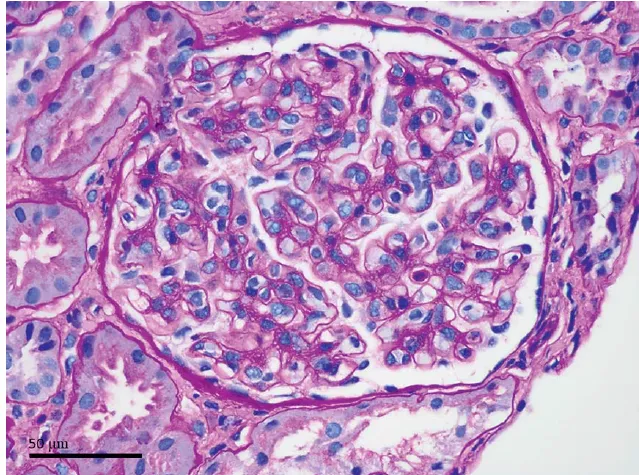

Foi feito o diagnóstico de pielonefrite xantogranulomatosa.

A pielonefrite xantogranulomatosa, uma forma de pielonefrite crônica, está tipicamente associada à obstrução por cálculos e infecções recorrentes do trato urinário. As complicações podem incluir abscessos e fístulas. A perda da função renal é comum, e a nefrectomia é o tratamento definitivo. O paciente recebeu alta 5 dias após a cirurgia e apresentava-se bem, com função renal estável, após 1 mês de acompanhamento.

Uma causa incomum de hematúria glomerular intermitente!

Uma causa incomum de hematúria glomerular intermitente!